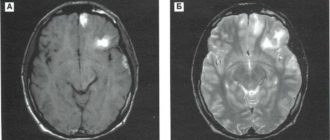

Единичный очаг левой височной доли

Невропатолог

Очаговое поражение головного мозга что это такое? Разрушение структур ЦНС бывает очаговым и диссеминированным,